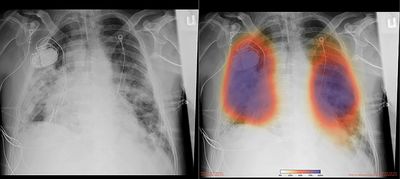

Researchers soon positioned quickly their program , wherever there was sign of lung damage or other signs of pneumonia the x-ray get dotted with color spot at that place.

a) simple X-Ray b)AI figured out X-Ray